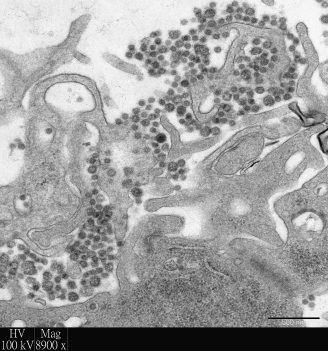

香港大學李嘉誠醫學院的研究人員利用其世界頂尖的「人類呼吸道外植體培養技術」研究新興呼吸道病毒,並在最新出版的刊物中發表可用於改善治療中東呼吸綜合症 (MERS) 的研究成果。研究證明結合使用目前已獲得臨床使用許可的干擾素和環孢黴素,較使用單一藥物治療或零治療更能顯著抑制中東呼吸綜合症冠狀病毒在人類支氣管和肺部中複製及造成組織損傷。研究結果已於抗病毒治療領域的權威期刊《抗病毒研究》(Anti-viral Research)發表。(按此瀏覽期刊文章)

由於過往利用細胞培養技術或實驗動物不能完全真實地呈現人類感染嚴重呼吸道病毒時的情況,香港大學病理學系黎國思教授以及公共衞生學院的陳志偉博士、陳韻怡博士、潘烈文教授及裴偉士教授於二零零五年共同研發「人類呼吸道外植體培養系統」,旨在為尋找以實驗室為本的方法研究嚴重呼吸道病毒感染,同時亦能更真實地反映疾病的機制及用於治療人類時的成效。

儘管香港至今尚未受中東呼吸綜合症影響,該病毒在中東地區已引發嚴重問題,並引致高達39%的死亡率。由於病毒與嚴重急性呼吸系統綜合症(SARS)病毒有關,中東呼吸綜合症已被世界衛生組織列為對全球公共衞生具重大威脅之一的疾病。這項研究結果將作為基礎,協助進一步評估這種新式治療策略可否應用於中東呼吸綜合症的人類臨床測試。